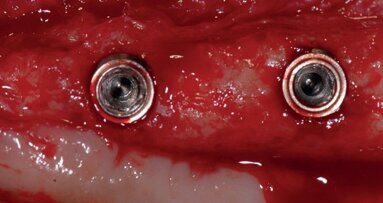

Six rabbits received 24 cylindrical dental implants and were placed in two groups (n = 3 per group): control group, with smooth surfaces; and test group, with the SLA surface treated with TiO2 microparticles. All of the animals were sacrificed after four weeks. Half of the implants (one per animal from each group) were used to test removal torque values and half of them were used for the histological analysis.

Reverse torque was significantly different between the groups (p = 0.0001). The histological analysis showed higher degrees of bone organization in surface samples from the test group.

Results indicate that blasting implant surfaces with TiO2 particles is an appropriate treatment option, with minimal risk of contamination by residual debris from the procedure.